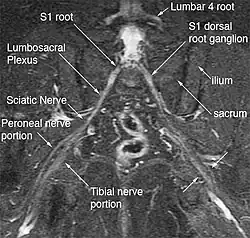

Bilateral split sciatic nerve

The most significant impact of magnetic resonance neurography is on the evaluation of the large proximal nerve elements such as the brachial plexus (the nerves between the cervical spine and the underarm that innervate shoulder, arm and hand),[9] the lumbosacral plexus (nerves between the lumbosacral spine and legs), the sciatic nerve in the pelvis,[10] as well as other nerves such as the pudendal nerve[11] that follow deep or complex courses.